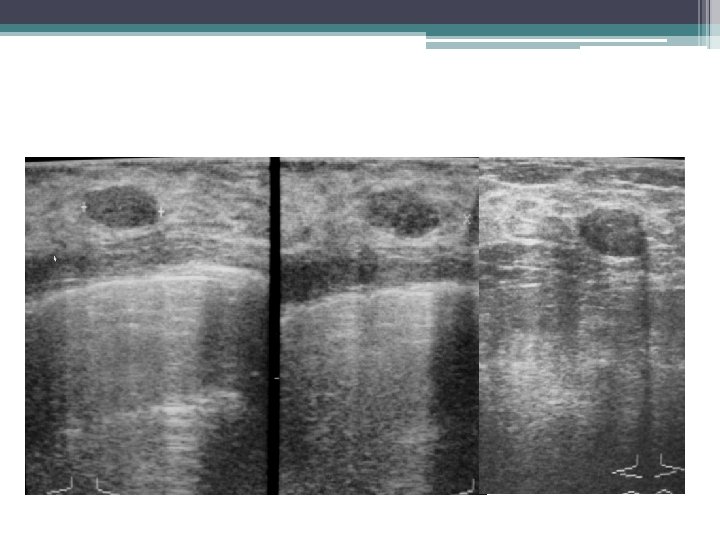

KYSTE DU SEIN • ECHOGRAPHIE: examen clé ▫ Aspect typique: �lacune transonore, à limites nettes, sans ou avec paroi fine régulière. �net renforcement postérieur ▫ Aspect atypique: �liquide épais, paroi épaisse, végétations internes, cloisons �diagnostic différentiel avec : �Adénofibrome, hématome, abcès �Cancer du sein

ADENOFIBROME ECHOGRAPHIE: • Forme typique: ▫ Nodule ovale à grand axe transversal ▫ Contours nets et réguliers. ▫ Hypoéchogène homogène avec renforcement postérieur, cônes d’ombre latéraux ▫ Mobile et compressible sous la sonde • Les formes atypiques sont fréquentes: ▫ lésions solides ne réunissant pas tous les critères de bénignité ▫ atténuation post (composante fibreuse et/ou calcique).